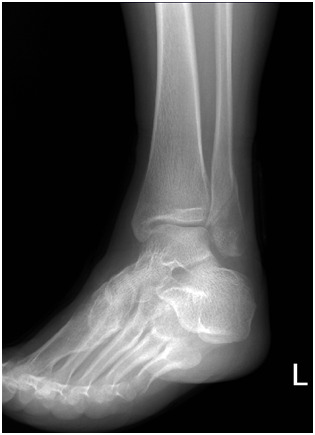

수술전]